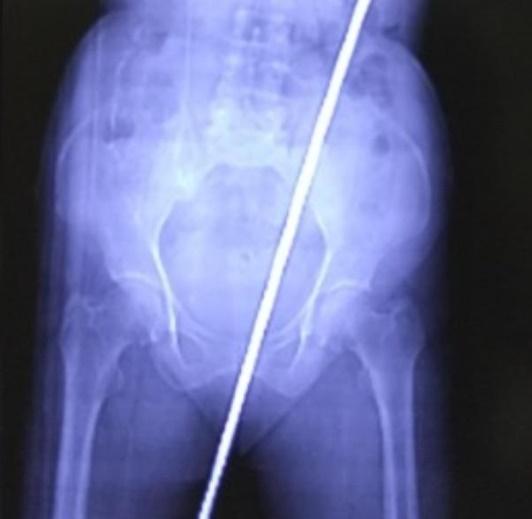

婦人一跌慘被2呎長鐵棍貫「後門」,牛屎鐵鏽入肚。(CT影像。網上圖片)

婦人被送到當地的卡斯圖爾巴醫學院搶救,透過X光和電腦斷層(CT)等檢查發現她被一支長達60厘米的生鏽鐵棍刺穿臀部,直插體內,她的肛管(anal canal)、直腸都被刺破,她的糞便亦流入體內,慶幸輸尿管、主動脈以及腎臟等重要部位都沒有受傷。醫生立即為她進行手術,順利將鐵棍移除,注射破傷風針與抗生素以避免感染後。手術後,婦人除了初期的噁心、腹痛、無法行走外,已經逐漸恢復,最後留院10天已可回家休養。